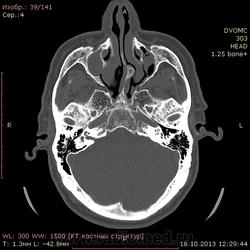

72 года. Жалобы на частые головные боли. В мозгах вроде ничего особенного, а вот пазухи...лобной нет, клиновидная недоразвитая. Вопрос вот какой:

Можно ли считать картину в, опять таки недоразвитых, верхнечелюстных пазухах (особенно слева) как хронический гайморит?(или острый такой бывает?) вся эта неоднородность и полости воздушные и мягкотканная плотность....

Написал бы как дополнение: двусторонее нарушение пневматизации в обеих в/ч, справа тотальное, слева субтотальное вспененными плотностями. Синусит? в правой в/ч возможно, полипозный (или кистознополипозный, как вам больше нравится). Рек. конс. ЛОР.